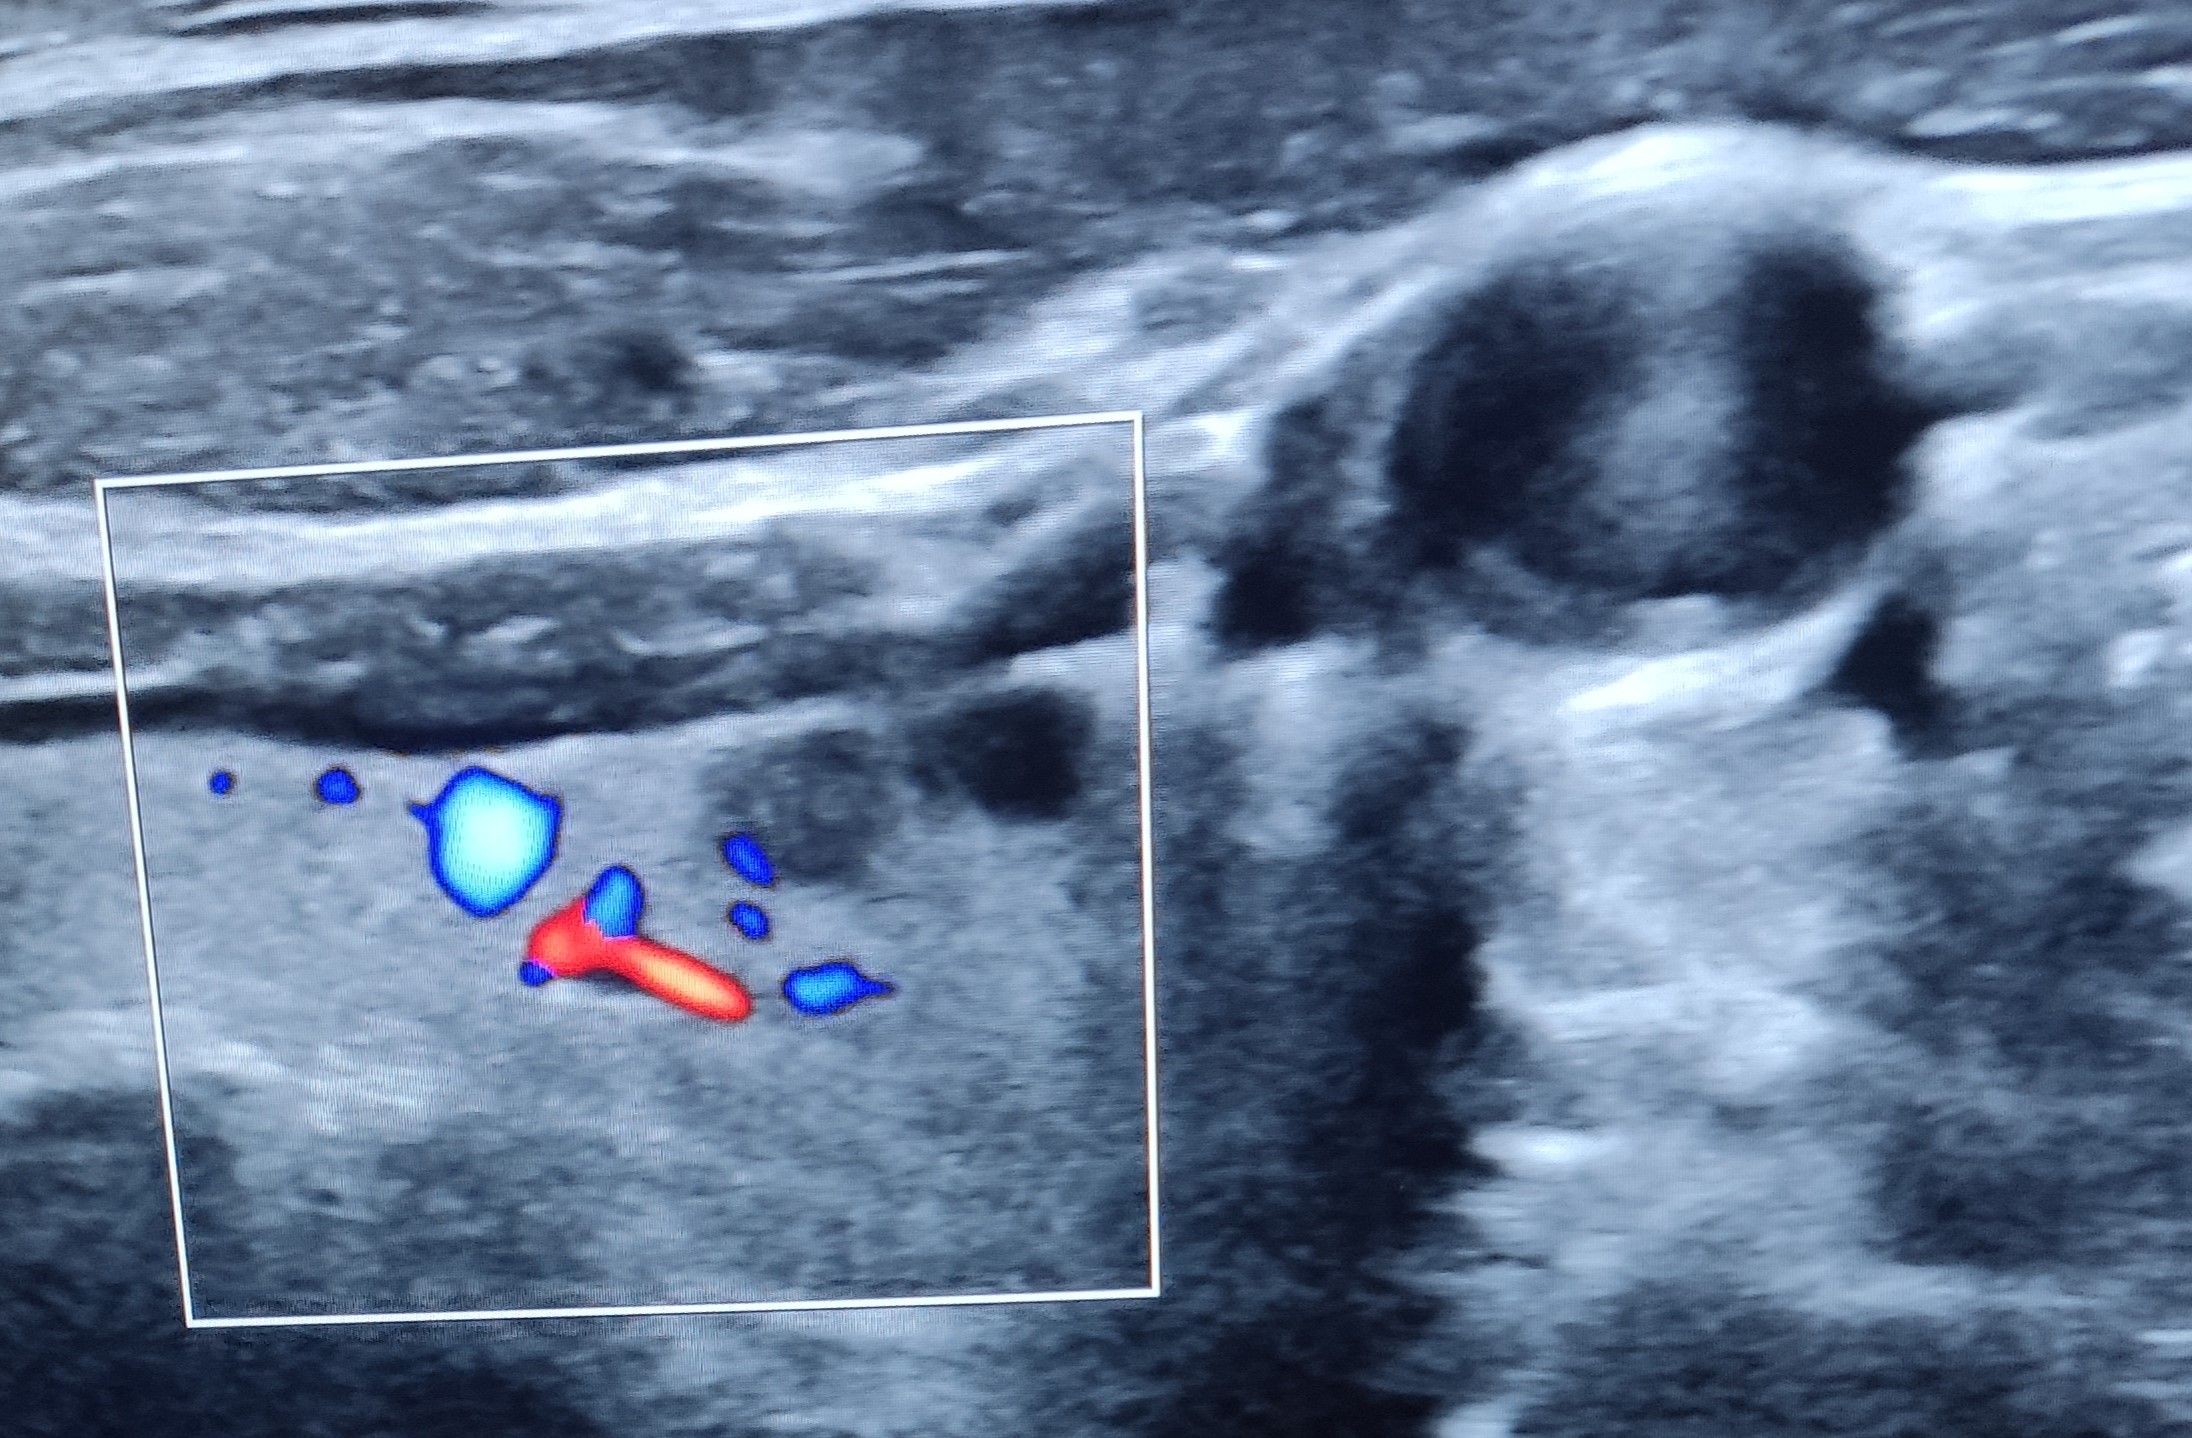

En la ecografía realizada en consulta se realizan diferentes mediciones, descartando hipertrofia glandular o bocio. Explorando ambos lóbulos posteriormente, se objetivan dos imágenes quísticas, subcentimétricas, anecoicas, con bordes bien definidos y refuerzo posterior, todo ello compatible con quiste benigno, de contenido posiblemente líquido o coloide, sin captación de Doppler.

En el lóbulo izquierdo se objetiva una lesión algo mas hiperecogenica, tambien subcentimetrica, sin captacion de dopler color ni refuerzo posterior, que impresiona de contenido algo sólido, con bordes bien definidos y regulares.